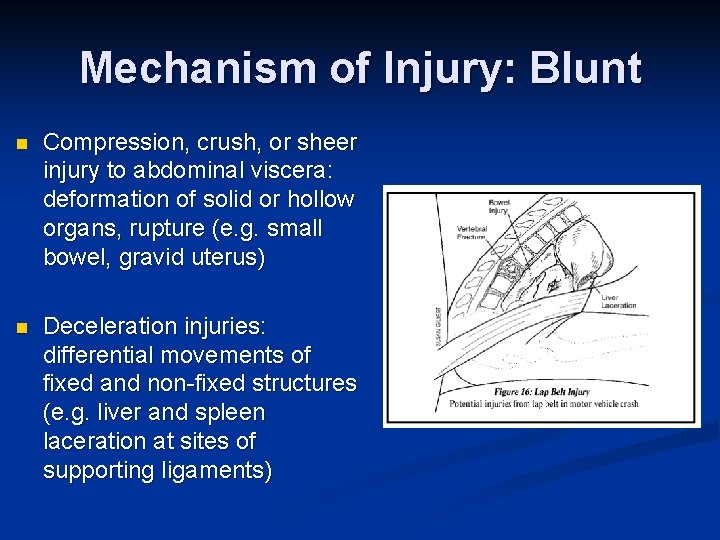

Mechanism of Injury: Blunt n Compression, crush, or sheer injury to abdominal viscera: deformation of solid or hollow organs, rupture (e. g. small bowel, gravid uterus) n Deceleration injuries: differential movements of fixed and non-fixed structures (e. g. liver and spleen laceration at sites of supporting ligaments)